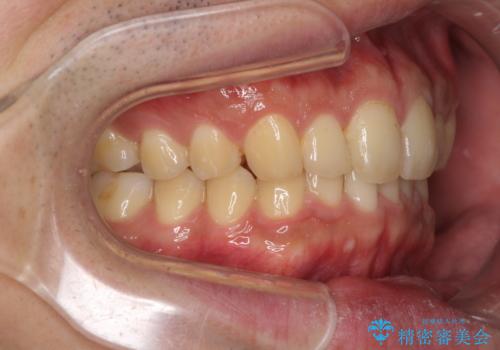

- 上下前歯のデコボコと下の前歯が隠れるほどの深い咬み合わせを気にして来院された患者様です。

インビザラインによる上下歯列の拡大と、IPR(歯と歯の間を削る)にるスペースの獲得により、口元のデコボコとディープバイトを改善することとしました。

デコボコがなくなったことで日頃の清掃が行いやすくなり、深い咬み合わせが改善したことで、食いしばりによる顎の負担も軽減されました。